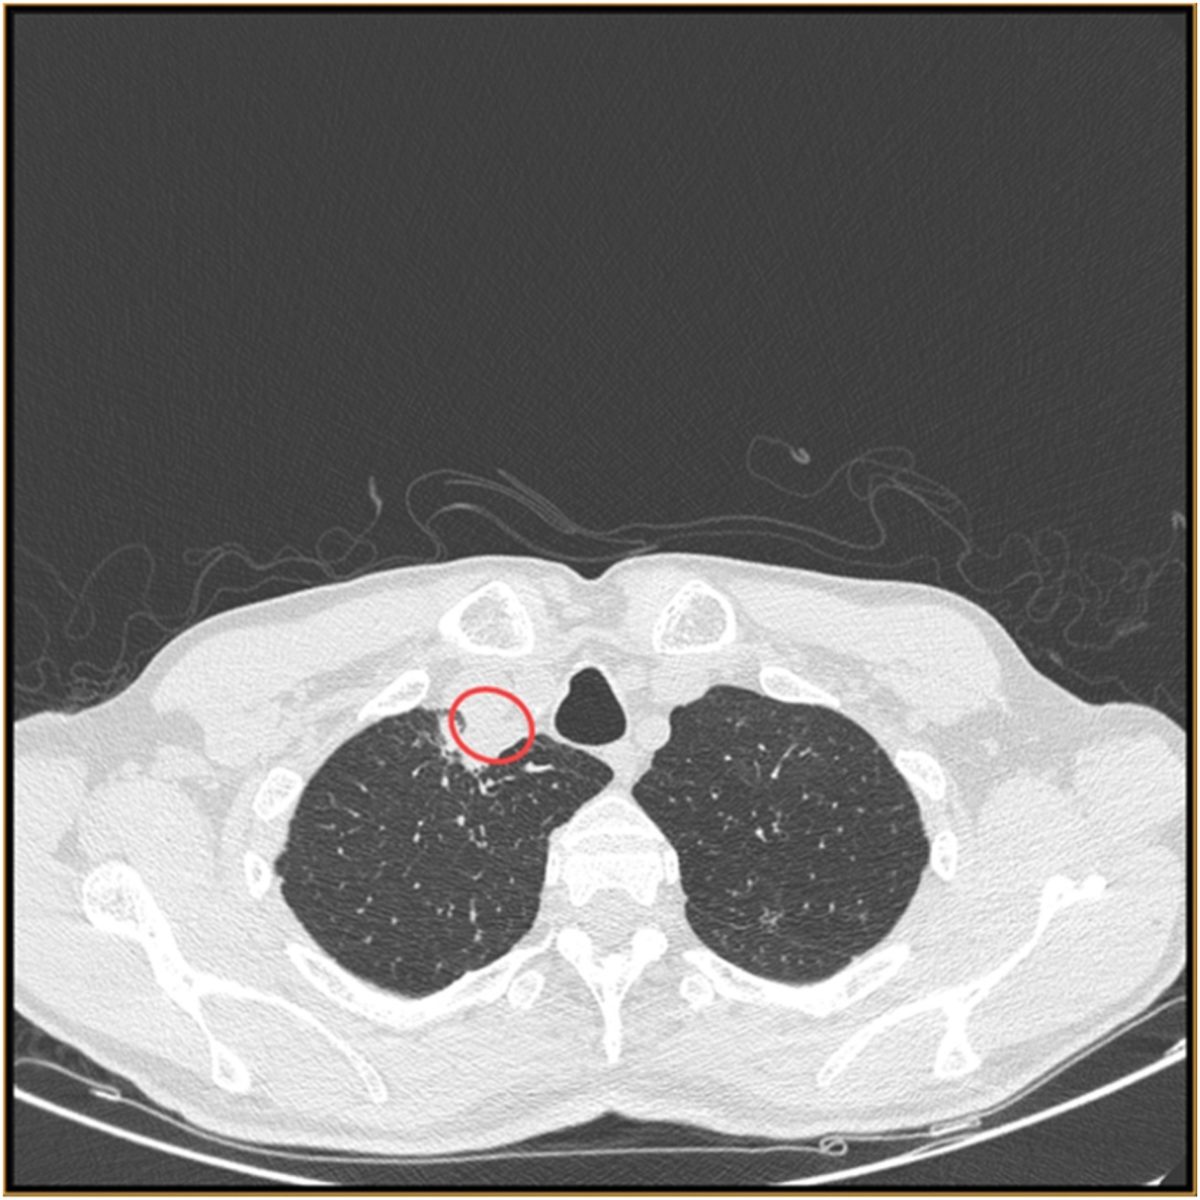

Ένας 61χρονος ασθενής από την ανατολική περιοχή της Ινδίας αναζήτησε ιατρική βοήθεια για μια σειρά από συμπτώματα, όπως βραχνάδα, κόπωση, βήχα και δυσκολία στην κατάποση. Μια ακτινογραφία θώρακος στο νοσοκομείο φαινόταν φυσιολογική, αλλά μια αξονική τομογραφία που έγινε στον λαιμό του έδειξε ένα απόστημα. Από αυτό οι γιατροί πήραν δείγμα και στάλθηκε για ανάλυση.

Η αξονική τομογραφία έδειξε την παρουσία αποστήματος, Image credit Soma Dutta, Ujjwayini Ray/Medical Mycology Case Reports (CC by 4.0)